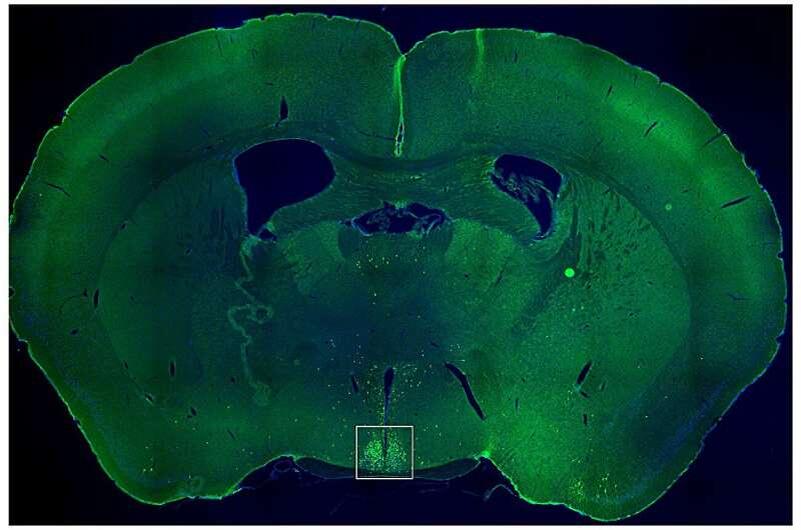

Учёные предположили, что в гипоталамусе — точнее, в супрахиазматическом ядре (SCN), где находятся клетки, задающие суточный ритм всему телу, — существует цепочка нейронов, управляющих именно «временем аппетита».

Чтобы разобраться, учёные использовали генно-модифицированных мышей, у которых можно было искусственно включать и выключать нужные нейроны.

Когда они активировали эти клетки посреди «дневного» покоя (около 10 утра, что для ночных животных — время сна), мыши начинали есть в два раза больше обычного.